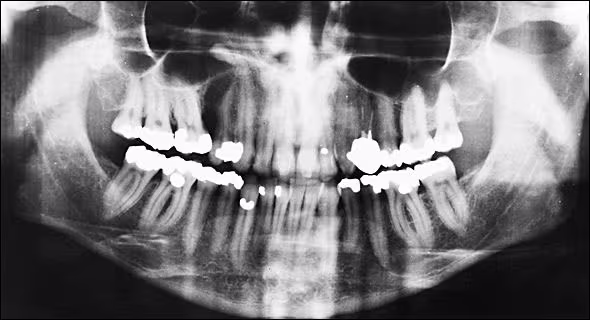

Preoperative Panoramic Radiograph This panoramic radiograph was taken prior to the third surgery. The osteolytic lesion between the maxillary right first molar and first premolar is not confined to the alveolar process but encroaches upon the maxillary sinus. A homogeneously radiopaque structure seems to be associated with the lesion.